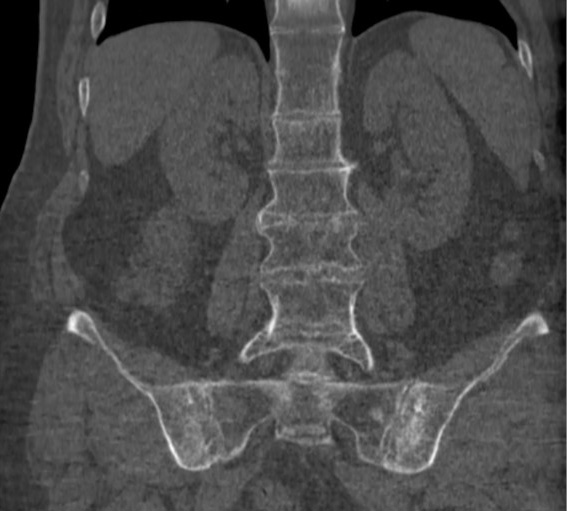

Болезнь Бехтерева (анкилозирующий спондилоартрит) ― разновидность хронического ревматического воспаления. Воспаление поражает в первую очередь позвоночник и крестцово-подвздошные сочленения (рис. 1), которые соединяют позвоночник с тазом. Болезнь обязана своим названием русскому неврологу Владимиру Михайловичу Бехтереву, впервые описавшему это состояние в начале XIX века [1].

Рис. 1. Рентгенограмма пояснично-крестцового отдела позвоночника пациента с болезнью Бехтерева: на снимке визуализируется анкилоз крестцово-подвздошных сочленений и поясничных позвонков.